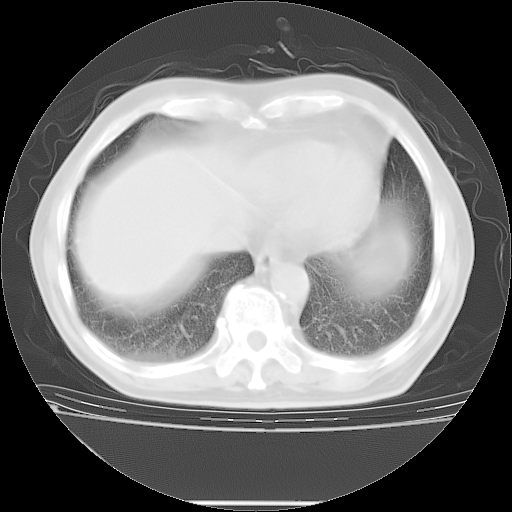

胸腹部CT,诊断意见:左上肺叶钙化灶、左侧胸膜局限性增厚并钙化、胆囊炎。描述部分肺组织呈磨玻璃样改变。